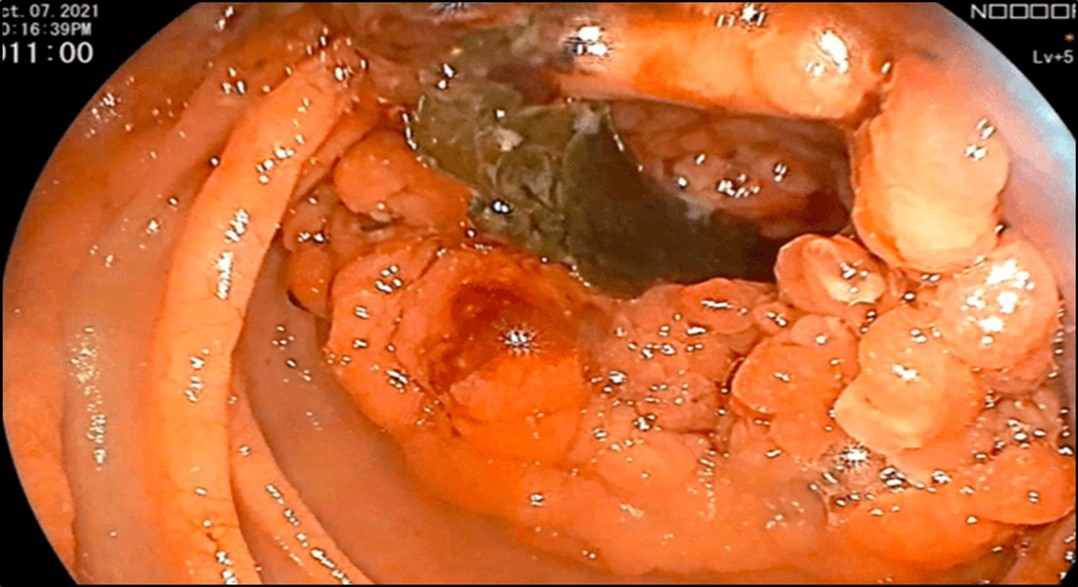

Esophagogastroduodenoscopy (EGD) revealed a fistulous opening in the third part of the duodenum and a bleeding vessel. (Figure 1) Bleeding was controlled with injection hemostasis and 3 hemoclips were deployed. The colonoscopy revealed a large obstructing, polypoid, ulcerating, and circumferential mass with areas of necrosis that was seen at the proximal transverse colon which precluded further advancement of the scope. Biopsy samples were sent for histopathology investigation and TB polymerase chain reaction (PCR) test.

Figure 1.EGD findings of a pathologic lumen and a bleeding vessel were seen at the third portion of the duodenum.

EGD findings of a pathologic lumen and a bleeding vessel were seen at the third portion of the            duodenum.